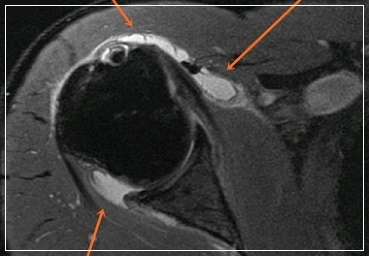

오십견은 비교적 흔한 병이라 쉽게 생각할 수 있지만 방치하다 치료시기를 놓치면 후유증이 커질 수 있습니다. 또한 회전근개 파열, 석회화 건염, 목 디스크 등 다른 원인이 될 수 있는 질환과 구별을 해야 하기 때문에 통증 초기에 정확한 진단적 검사와 진료를 받는 것이 필요합니다. 치료하지 않을 경우 증상이 1~2년 이상 지속되어 생활에 많은 불편을 초래할 수 있습니다.